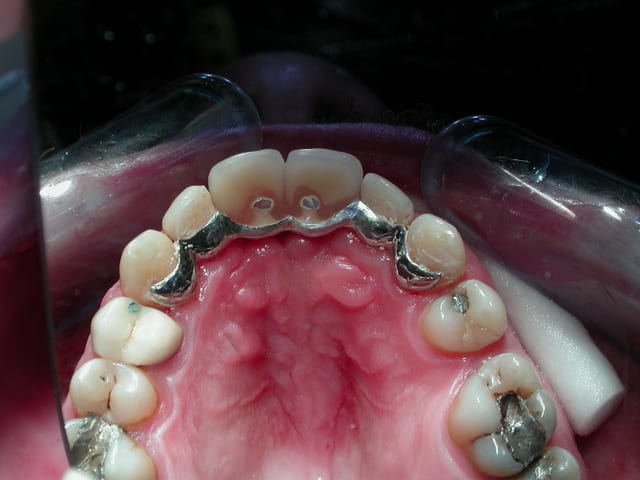

Comme je n'ai pas pu trouver la marque de l'implant, j'ai du me débrouiller autrement pour dépanner ce patient( à la cmu).

Voilà quelques photos de l'étape provisoire et du definitif avec un ancrage dans l'impant et des ailettes palatines.

Un grand merci à mon prothésiste.

Son dentiste étant en république tchèque et qu'il n'a pas l'intention de retourner dans son pays, j'avais quel choix.

Étant en plus à la CMU je ne pouvais pas lui proposer de traitement idéal (Dépose de l'implant + greffe + 2 implants+ 2CCM).

Et puis ce patient présente un problème cardiaque qui contre indique la dépose de l'implant.

Donc je pense avoir réaliser un traitement correct avec ce que j'avais de disponible comme matière et le patient est satisfait. N'est ce pas l'essentiel!!!!